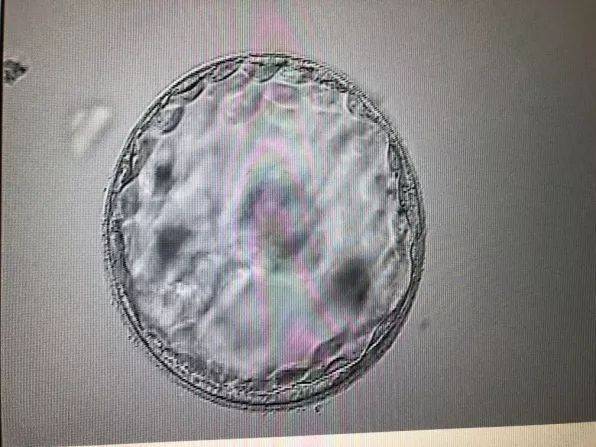

- 胚胎长啥样 40天胚胎长什么样子图片05-24